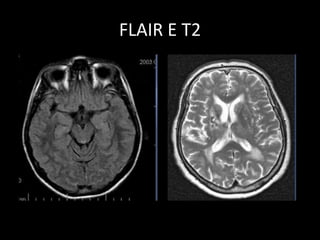

• Utilizada em exames de crânio.

• T2, mas o líquido fica preto (sem

sinal)-TI longo.

• Utiliza um pulso de inversão pra

saturar o sinal do LCR.

FLAIR

• Imagens de lesão no parênquima

cerebral serão evidenciadas no

FLAIR.

• Sequência mais importante no

estudo do encéfalo.

FLAIR E T2

• Utilizada emexames de crânio. • T2, mas o líquido fica preto (sem sinal)-TI longo. • Utiliza um pulso de inversão pra saturar o sinal do LCR. FLAIR

• 45.

• Imagens delesão no parênquima cerebral serão evidenciadas no FLAIR. • Sequência mais importante no estudo do encéfalo. FLAIR